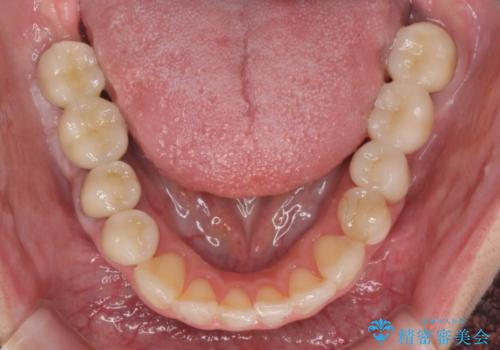

インプラント・セラミック・矯正治療を含む包括歯科診療

- 20代女性

- 「地元の歯医者にずっと通っているが、どんどん歯が悪くなる。時間とお金がかかってもいいので徹底的に歯を治したい。」

、と総合的な歯科治療を希望されて来院されました。

虫歯や咬合関係・歯槽骨の吸収・根尖病変・歯の欠損・複合的な問題を一つずつ解決し、

安定した噛み合わせの構築・歯ブラシのしやすい環境の整備・歯内歯周の感染除去・造骨を伴うインプラント治療

を行い、長期的な予後を見込める口腔内環境を確立、整備して行きます。